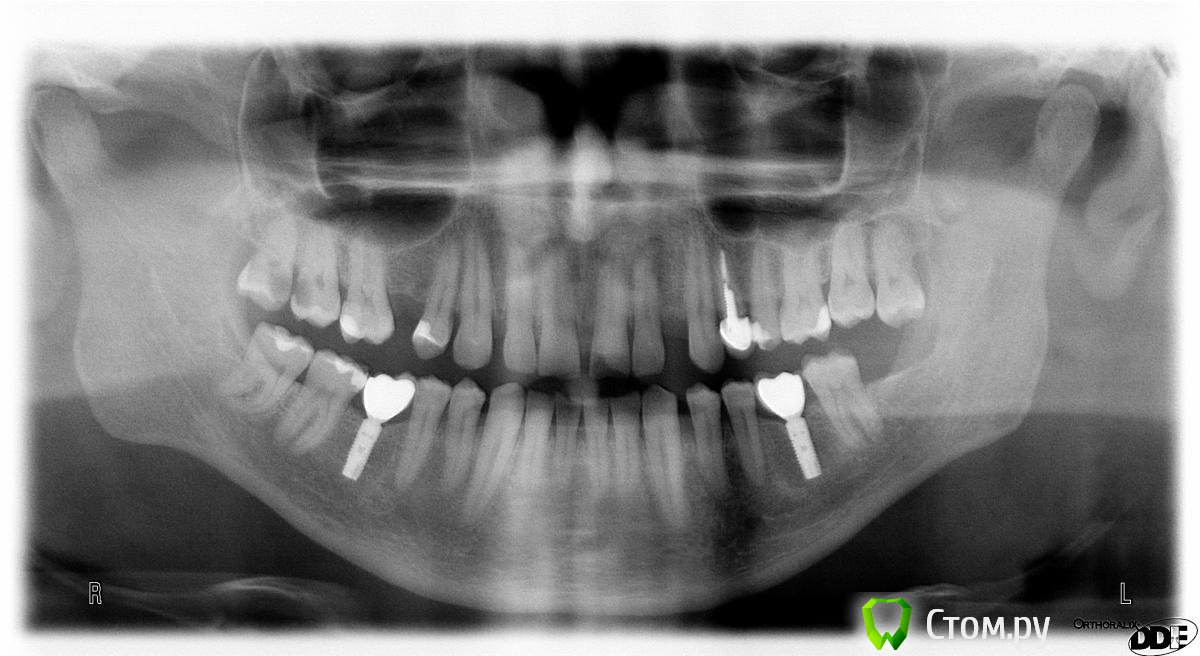

vinstom Опубликовано 25 мая, 2014 Автор Поделиться Опубликовано 25 мая, 2014 Может это поможет в споре. Покопался в истории нашел ОРТО за 2012 год. Т.е. три года, после нагрузки. Можно сравнить ситуацию, очень наглядно. 1 Ссылка на комментарий

Bobby Опубликовано 25 мая, 2014 Поделиться Опубликовано 25 мая, 2014 Может это поможет в споре. Покопался в истории нашел ОРТО за 2012 год. Т.е. три года, после нагрузки. Можно сравнить ситуацию, очень наглядно.Доктор, аккуратно работаете. Красиво. Спасибо за снимок. Ссылка на комментарий

Doc Опубликовано 25 мая, 2014 Поделиться Опубликовано 25 мая, 2014 Кстати, для пяти лет функционирования (топикстартер указал 2009 год, как дату фиксации) на том же Нобеле, подобная ремоделировка вообще является нормой. Вспомним пресловутые 1,5 мм в первый год и 0,2-0,5 каждый последующий. Если на Астре через пять лет и три недели перелома ремоделировка достигла того уровня, который у большинства других систем считается нормой, то это далеко не самый плохой результат. Хотя, конечно, один клинический случай ничего не доказывает. 1 Ссылка на комментарий